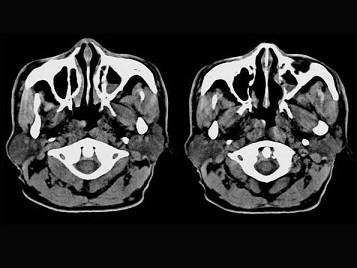

问题 男,61岁,流鼻血三天。如图所示最可能的诊断为 ( )

选项 A、小唾液腺瘤 B、鼻咽部息肉 C、鼻咽腺样体增生 D、鼻咽纤维血管瘤 E、鼻咽淋巴滤泡增生

答案 E